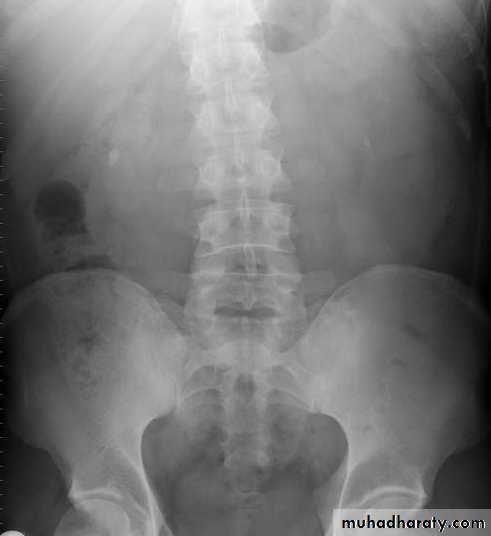

The IVU series consist of:1-KUB film…To identify any calcification like stones or nephrocalcinosis.

KUB

CALCULIMost renal stones are calcified and show varying density on plain x-ray films.

Pure uric acid & xanthine stones are radiolucent on plain radiography, but are well seen at CT or US.

Plain film is more sensitive than US for detecting ureteric calculi.